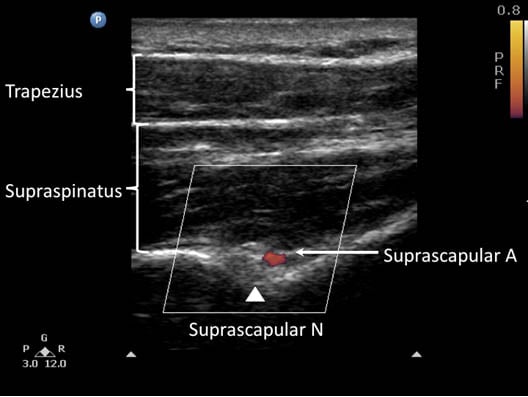

When imaging the suprascapular fossa with the ultrasound, the two key muscles in the scan are the trapezius and supraspinatus muscles (Figure 4). The suprascapular nerve is often seen accompanied by the suprascapular artery on the floor of the scapular spine between the suprascapular notch and spinoglenoid notch. The scapula spine forms an angle (39.50 ± 5.80) to the axis of the scapula blade[15] thus orientation of the ultrasound transducer should be closer to the coronal plane in order to visualize the contents of the suprascapular fossa.

Block Technique

The patient can be sitting or prone. The scapula spine, coracoid process and acromion are used as palpable landmarks. Ultrasound scanning is performed with a linear ultrasound transducer (7-13 MHz) placed in a coronal plane over the suprascapular fossa with a slight anterior tilt. The transducer is oriented such that it is perpendicular to the line joining the coracoid process and the acromion (reflecting the position of the spinoglenoiod notch). The supraspinatus and trapezius muscles and the bony fossa underneath them should come into view (Figure 5). By adjusting the angle of the ultrasound transducer in a cephalo-caudad direction, the suprascapular nerve and artery should be brought into view in the trough of the floor. The nerve can sometimes be difficult to visualize as it has an approximate diameter of 25 mm.[19]